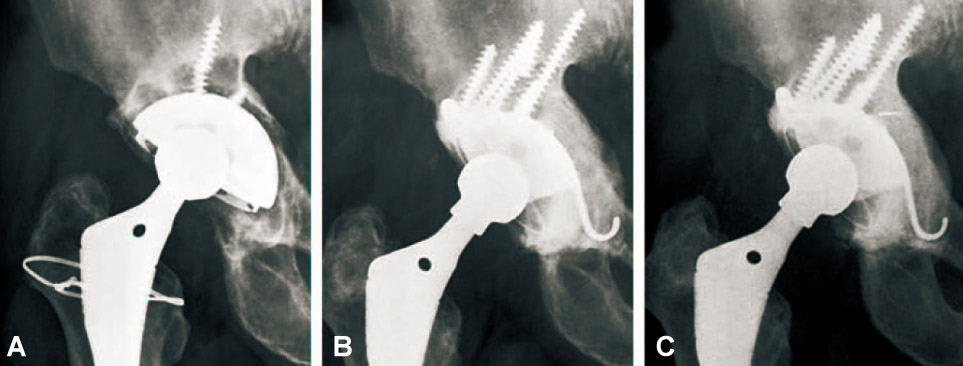

Thirty-six acetabular revisions were performed in 36 patients with use of the reinforcement ring and structural or morselized allograft, between 1997 and 2005, in thirty-six patients. According to the AAOS classification, thirty-four cases of acetabular defects were Ttype III, and two were Ttype IV. Mean follow-up period after surgery was 7.2 years.

The mean Harris hip score was 92.3, which was significantly increased compared with the preoperative score. (p<0.001). There were five failures: a case of aseptic loosening of Muller ring, two cases of infection (5.4%) and two cases of hip dislocation (5.4%). Graft incorporation and bone remodeling occurred successfully in all hips, but in the case of aseptic loosening in which the ring fixation had been inadequate at the time of surgery. The success rate was 91.7% with a mean follow-up of 7.2 years, if the cases of revision or loosening of the component were classified into failure cases.

Patients treated with acetabular revision with three kinds of reinforcement ring had reconstitution of periacetabular bone stock as well as good clinical and radiographic results. For the good results, the secure implant fixation during the surgery should be confirmed and we should completely understand the characters of the each kinds of reinforcement rings.